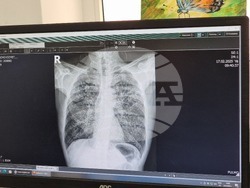

По-голям интерес на отминалите Дни на отворените врати, насочени към превенция на заболяването туберкулоза, отчетоха от Многопрофилната болница за активно лечение „Д-р Ат. Дафовски“ в Кърджали.

По думите на д-р Диана Вълчева, завеждат Пневмофтизиатрично отделение, от кампанията са се възползвали 21 души, като няма констатиран случай на туберкулоза.

Началникът на Пневмофтизиатрично отделение отчете, че броят на заболелите пациенти на болницата е средно между 23 и 25, като за миналата година те са били 25 души, а от началото на настоящата година досега са регистрирани 17 случая, три от които са на извънбелодробна туберкулоза и 14 на белодробна.

Д-р Вълчева отчете също, че през последните няколко години, особено след ковид пандемията, в региона се наблюдава нарастване на заболяванията на дихателната система, като става въпрос не само за респираторни и вирусни инфекции, но също така пневмонии и онкологични заболявания.

„Много се повиши броят на болните с белодробна фиброза. Това са хора, преболедували ковид“, каза още тя. По думите ѝ, след 2020 г. отделението няма сезонност на натовареността и спад на пациентите през летните месеци.